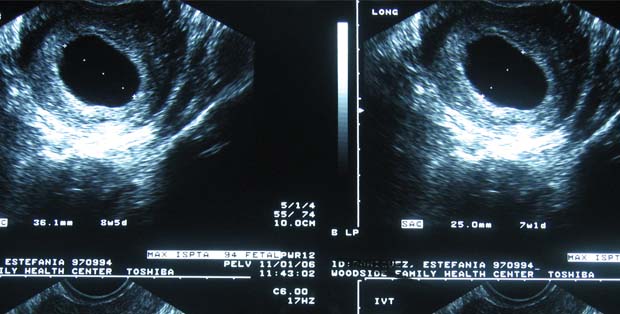

Ukuran Kantong Janin 6 Minggu Yang Normal Dan Tidak Bermasalah - Hamil.co.id

Ukuran Kantong Janin 6 Minggu Yang Normal Dan Tidak Bermasalah - Hamil.co.id